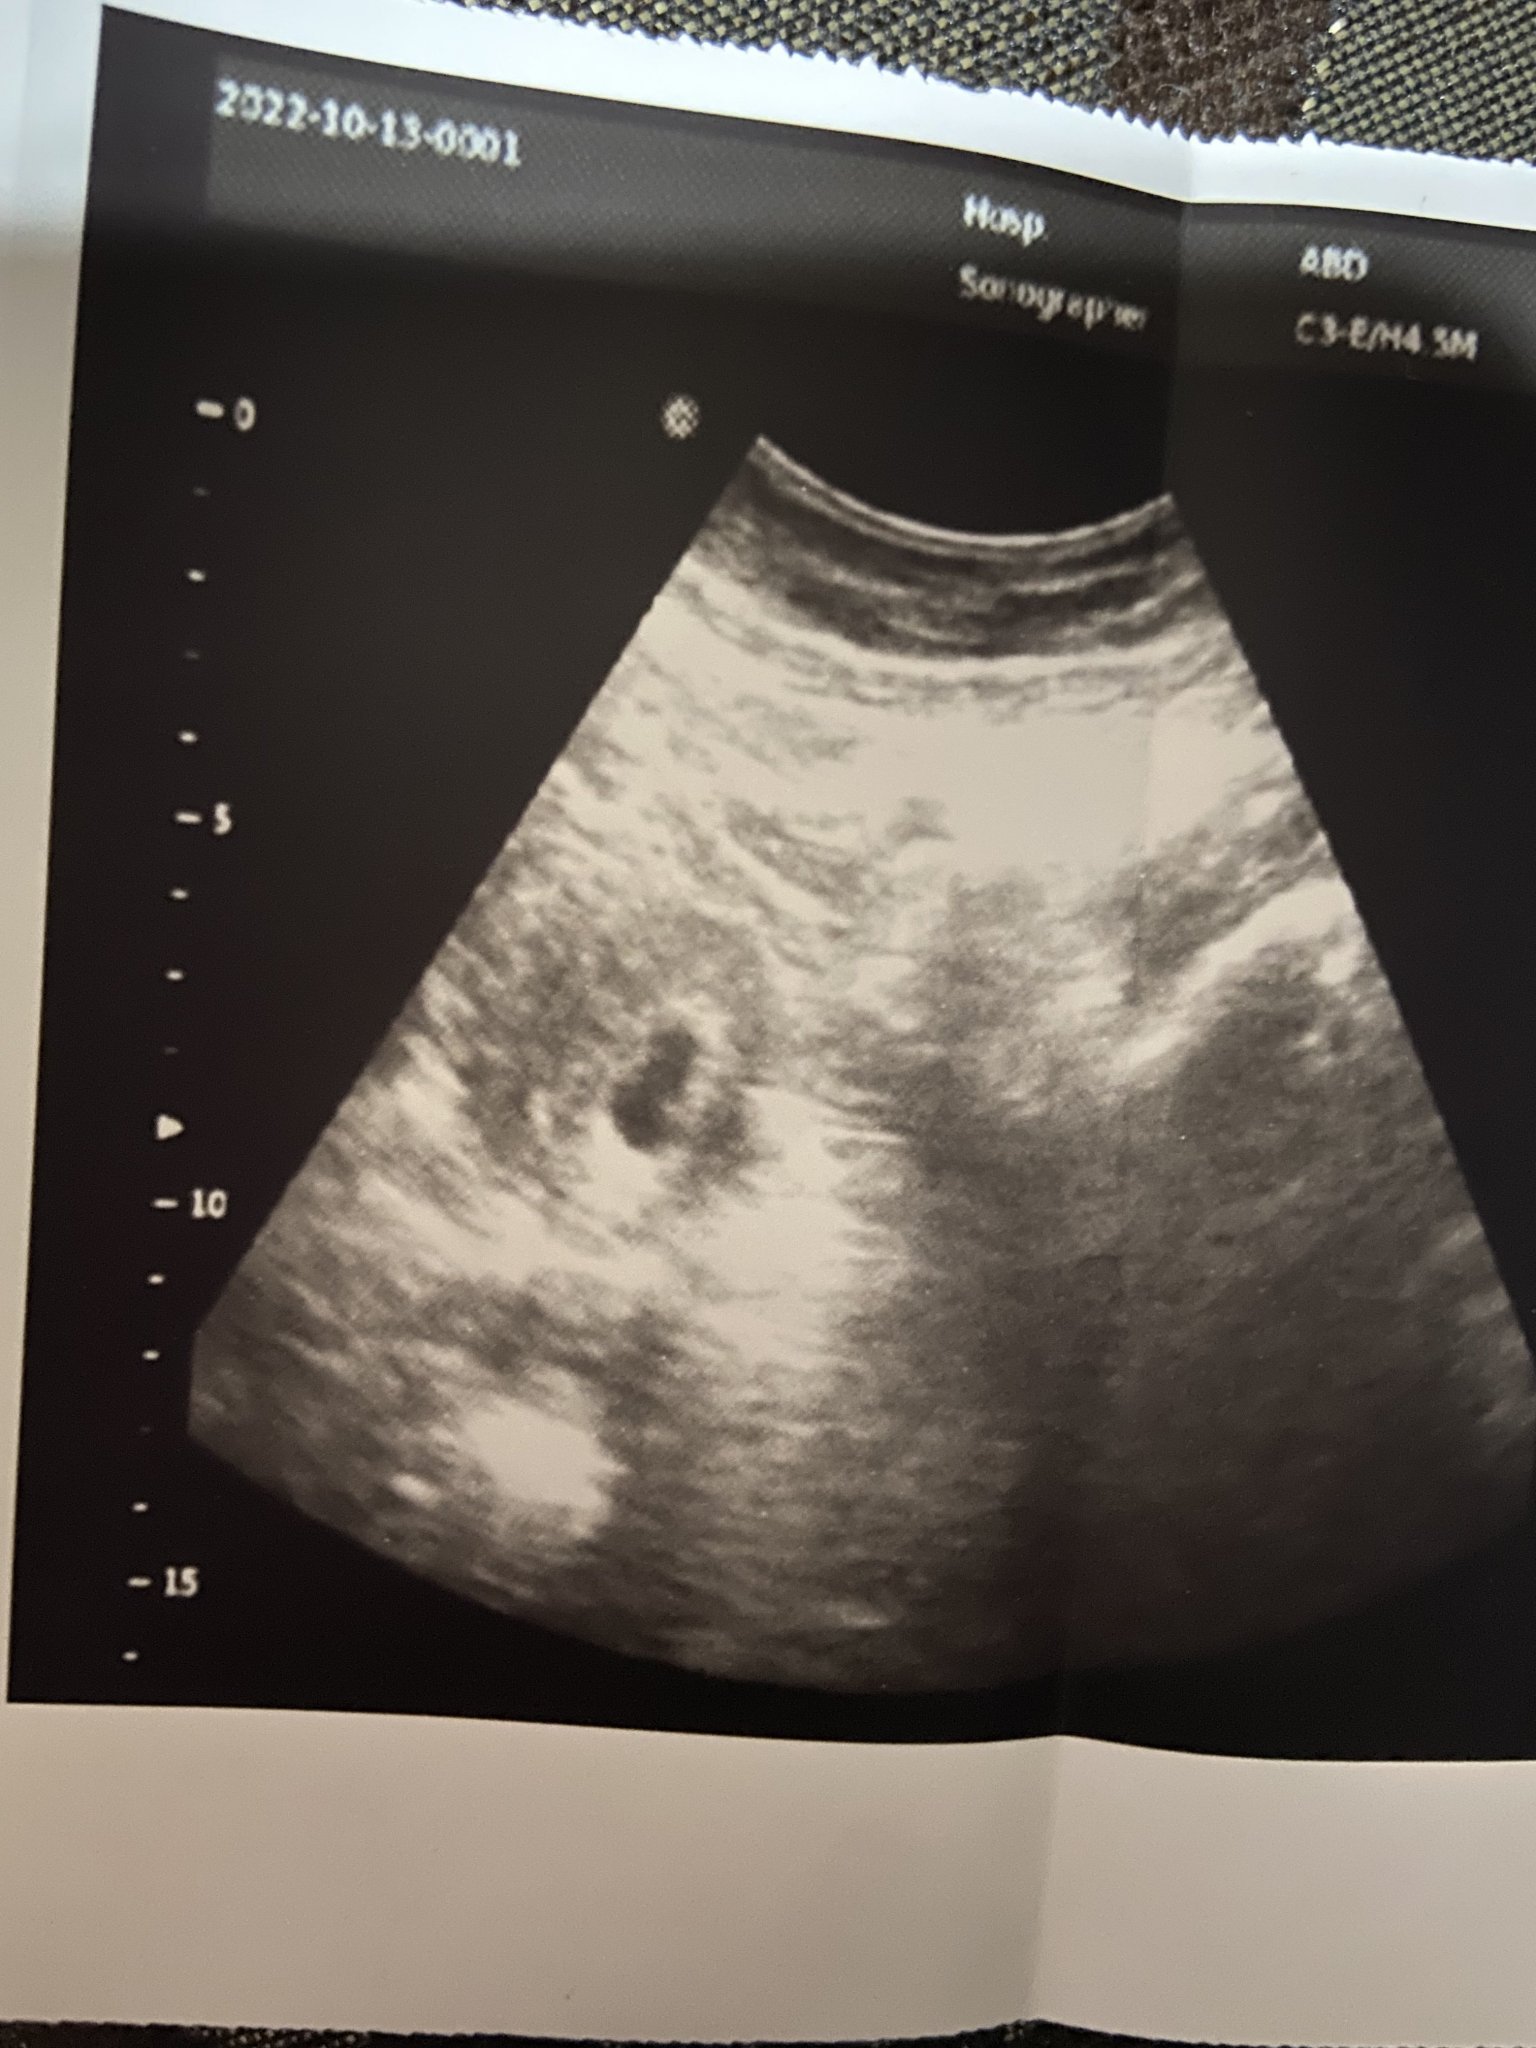

Това е снимка от 13-ти октомври , ден след прокървяването на 12-ти октомври, всичко изглежда супер и сакчето , а и точката вътре. Това е снимка от 6г.с 3 ден по мойте сметки.

Сака излизал в 6 седмица дефакто сака не отговарял, а и вътре само мехурче.

Отвратително грозен сак ,направо нищо общо с първата снимка и тази.